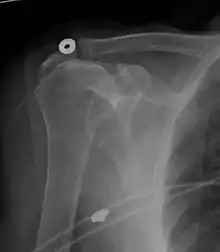

Diagnostic modalities, dependent on circumstances, include X-ray, MRI, MR arthrography, double-contrast arthrography, and ultrasound. Although MR arthrography is currently considered the gold standard, ultrasound may be most cost-effective.[31] Usually, a tear will be undetected by X-ray, although bone spurs, which can impinge upon the rotator cuff tendons, may be visible.[32] Such spurs suggest chronic severe rotator cuff disease. Double-contrast arthrography involves injecting contrast dye into the shoulder joint to detect leakage out of the injured rotator cuff[33] and its value is influenced by the experience of the operator. The most common diagnostic tool is magnetic resonance imaging (MRI), which can sometimes indicate the size of the tear, as well as its location within the tendon. Furthermore, MRI enables the detection or exclusion of complete rotator cuff tears with reasonable accuracy and is also suitable to diagnose other pathologies of the shoulder joint.[34]

MRI

Magnetic resonance imaging (MRI) and ultrasound[41] are comparable in efficacy and helpful in diagnosis although both have a false positive rate of 15–20%.[42] MRI can reliably detect most full-thickness tears although very small pinpoint tears may be missed. In such situations, an MRI combined with an injection of contrast material, an MR-arthrogram, may help to confirm the diagnosis. It should be realized that a normal MRI cannot fully rule out a small tear (a false negative) while partial-thickness tears are not as reliably detected.[43] While MRI is sensitive in identifying tendon degeneration (tendinopathy), it may not reliably distinguish between a degenerative tendon and a partially torn tendon. Again, magnetic resonance arthrography can improve the differentiation.[43] An overall sensitivity of 91% (9% false negative rate) has been reported indicating that magnetic resonance arthrography is reliable in the detection of partial-thickness rotator cuff tears.[43] However, its routine use is not advised, since it involves entering the joint with a needle with potential risk of infection. Consequently, the test is reserved for cases in which the diagnosis remains unclear.